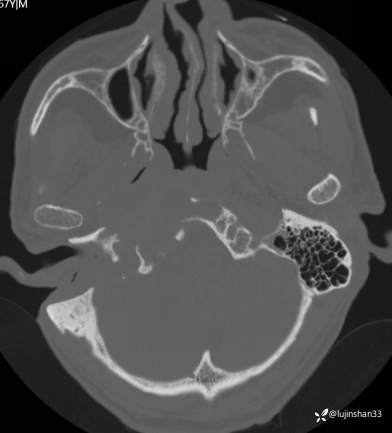

(2023-05-29 16:07,本院)CT颅脑:1、右侧颞骨全切除术后改变,术区见气体密度影,瘘管形成可能;术区多发软组织影,不完全除外炎性改变可能。2、左侧颞骨CT平扫未见明显异常。